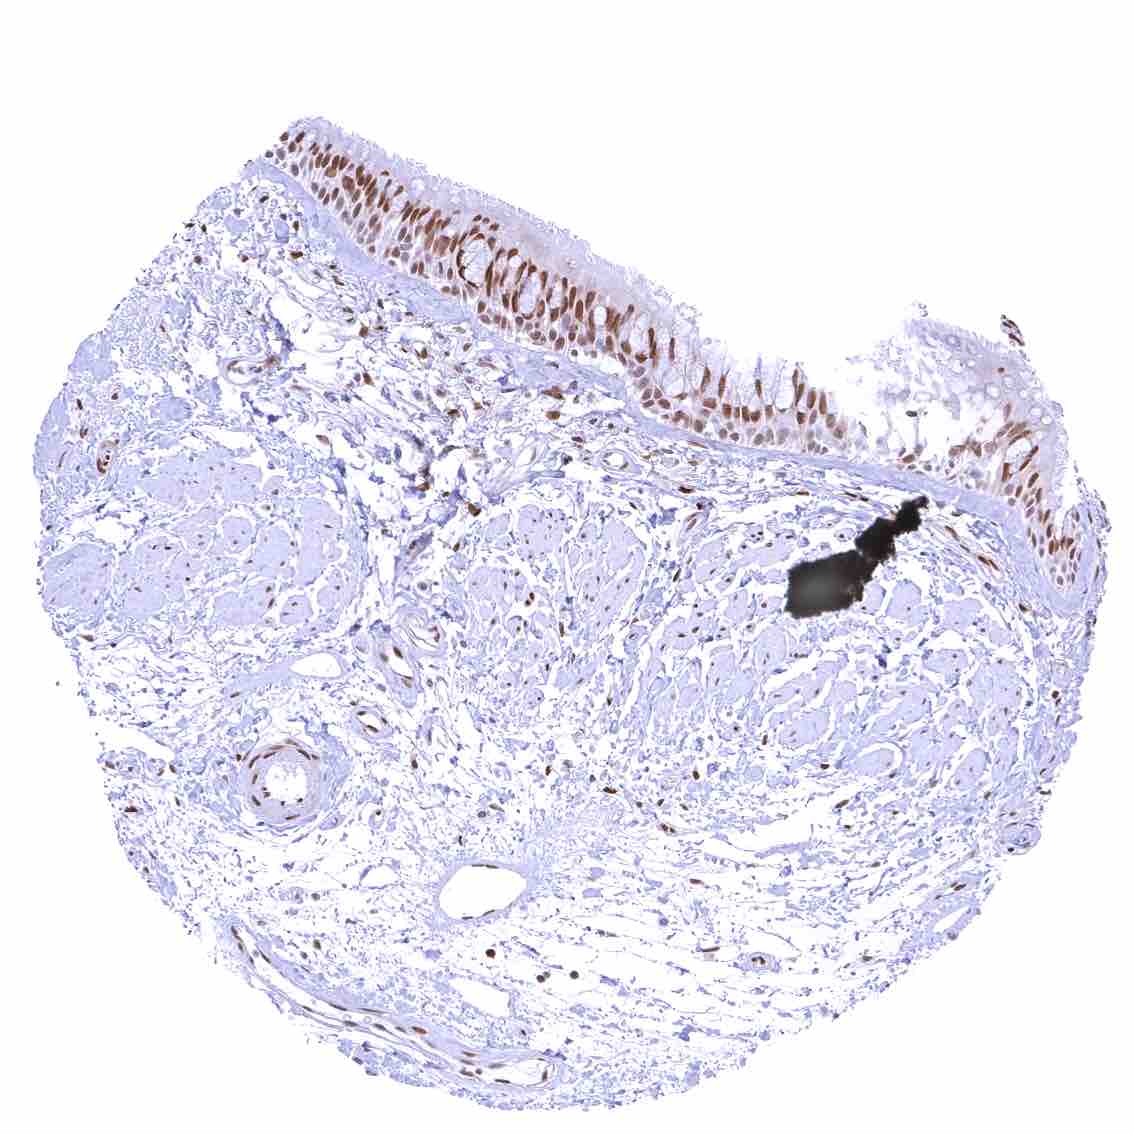

Tonsil, surface epithelium – Strong nuclear p27 staining of a significant subset of cells, especially in the interfollicular area. Nuclear staining of squamous epithelial cells predominates in the more mature cell layers (top 50_ of the epidermis)